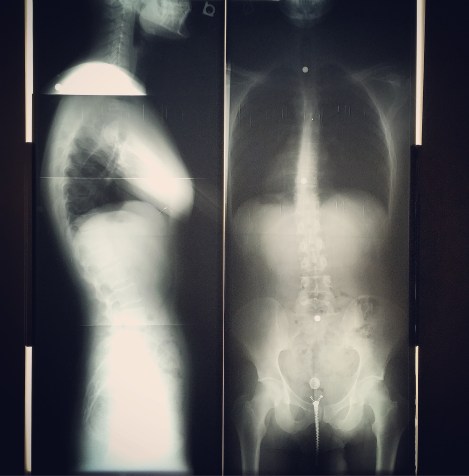

Chiropractic Care:

If you continue reading this week’s blog, you will get the pleasure of hearing all about my numb leg. It’s been very frustrating, and my symptoms are compounding. I’ve had a migraine the past two days, there has been a strange halo wavering around my eyeballs, I feel weak, and I was literally a thousand degrees this morning. I was sure death was near. I was pretty upset that I didn’t have my Limoges porcelain urn with the hieroglyphic inscription at the ready. I was also distraught that I wouldn’t die in Paris. I would be so annoyed to die anywhere other than Paris and even more irritated if I’m not interred in Père Lachaise. I can’t end up in some boring graveyard. So, in a panic, and eager for a good story, I dashed out of work and hurried to the chiropractor. It was not as terrifying as I expected. The doctor was very nice and we laughed about how out of line my spine was. I was just chuckling because I was dead inside. It was cool to see my skeleton, though. I don’t think I’ve ever seen my bones. Isn’t it strange to think about a skeleton living inside of you? Maybe that’s just me. MANDATORY DANCE INTERLUDE:

After my X-rays, he started cracking me up…my bones, not jokes…and that was a bit intense. He popped me in places I didn’t know could be popped. As I stood up, I felt a bit better. Not like a LOT better, but this is apparently a process. I go again after work. I mean it would’ve been cool to be perfectly in shape again, but this will do. Go get your bones cracker, dear reader.